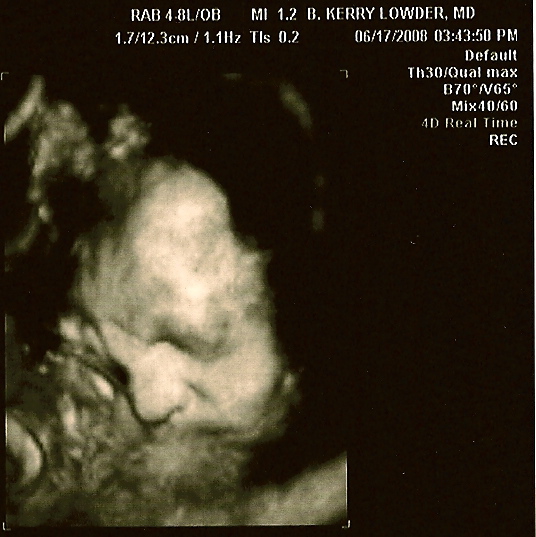

Im hedging my bets its another girl. these pics reminded me SO much of Brigittes 3d scan. Which means I can expect another little hairless Gabe wrapped in a blanket! I think its the nose that looks the same... here was Brigitte at 35 1/2 weeks